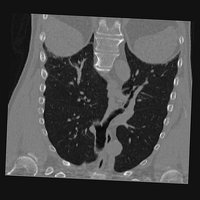

Exp. 3: Adult thorax data: To show the versatility of our approach we also apply it to adult thorax scans. For this experiment no organ specific training is performed but the whole volume is used. We evaluate reconstruction performance similar to Exp. 1 and Ti^^subscript𝑇𝑖\hat{T_{i}} prediction performance when ΩΩ\Omega is projected on an external plane, comparable to X-Ray examination using C-Arms. The latter provides insights about our method’s performance when applied to interventional settings in contrast to motion compensation problems. 60 healthy adult thorax scans were randomly selected, 51 scans used for ΩtrainsubscriptΩ𝑡𝑟𝑎𝑖𝑛\Omega_{train} and nine scans used for ΩvalidationsubscriptΩ𝑣𝑎𝑙𝑖𝑑𝑎𝑡𝑖𝑜𝑛\Omega_{validation}. Each scan is intensity normalised and resampled in a volume of 200×200×200200200200200\times 200\times 200 with spacing 1mm×1mm×1mm1𝑚𝑚1𝑚𝑚1𝑚𝑚1mm\times 1mm\times 1mm. Using the Fibonacci sampling method, 25 sampling plane of size 200×200200200200\times 200, evenly spaced between -50 and +50, were rotated over 500 normals. Training took approximately 20 hours for 60 epochs. Fig. 4c shows an example reconstruction result gaining 28dB PSNR with additional SVR. Ti^^subscript𝑇𝑖\hat{T_{i}} prediction takes approx. 20 ms/slice for this data.

Figure 4: (a): Comparison of a single slice from raw low-dose thorax CT data; (b): reconstruction based on SVRNet Ti^^subscript𝑇𝑖\hat{T_{i}} regression; (c): SVR initialized with SVRNet transformations after four iterations of SVR; (d): PSNR of (b) and (c) compared to (a). (e): shows a projection of an unseen pathological test CT volume as DRR and (e) shows a DRR at the location predicted by our method when presented with the image data in (e).

We use Siddon-Jacobs ray tracing [15] to generate Digitally Reconstructed Radiographs (DRRs) from the above described data. For training, we equally sample DRRs on equidistant half-spheres around 51 CT volumes at distances of 80cm, 60cm, and 40cm, between 90superscript90-90^{\circ} and 90superscript9090^{\circ} around all three co-ordinate axes. For validation, we generate 1000 DRRs with random rotation parameters within the bounds of the training data at 60cm distance from the volumetric iso-centre. We trained on healthy volunteer data and tested on nine healthy and ten randomly selected pathological volumes (eight lung cancer and two spinal pathologies). Our approach is able to predict DRR transformations relative to the trained reference co-ordinate system with an average translation error of 106mm and 5.6superscript5.65.6^{\circ} plane rotation for healthy patients, and 130mm and 7.0superscript7.07.0^{\circ} average error for pathological patients. An example is shown in Fig. 4e,f. Note that these values are good enough to robustly initialize intensity-based registration refinement. SVRNet prediction can be improved by generating a denser training data set, in particular, in more equidistant half-spheres.